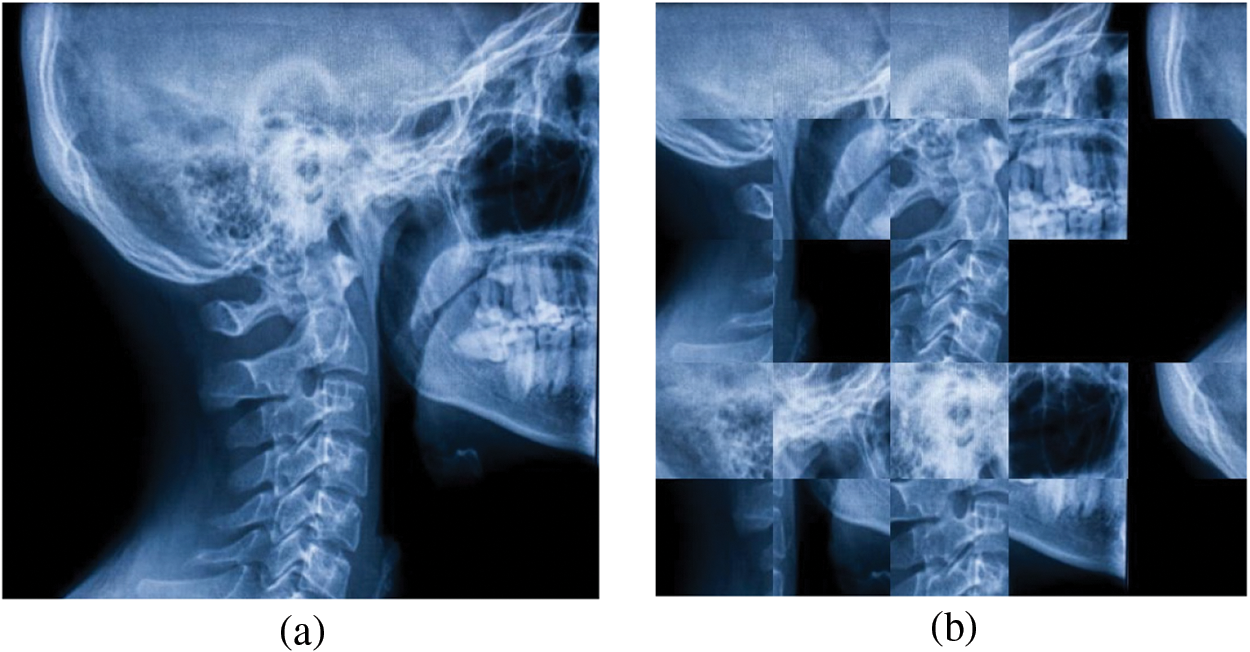

A sample implementation of Jigsaw transformation on the Skull X-ray image is depicted in Fig. 2.

Figure 2: A sample implementation of Jigsaw transformation on Skull X-ray image